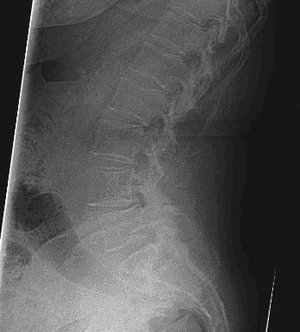

Röntgenbild der Lendenwirbelsäule zeigt Wirbelkörper und Bandscheiben deutlich.

Osteoporotisch bedingte LWK 2-Fraktur

Röntgenbild der Lendenwirbelsäule mit Wirbelkörperfraktur und Kyphoplastie.

Stabilisierung des Wirbelkörpers mittels Kyphoplastie LWK 2